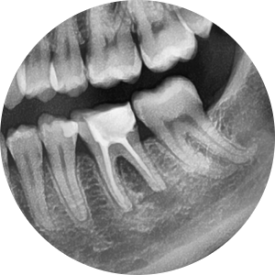

(좌측) 파노라마 엑스레이

(우측) 치근단 엑스레이

파노라마는 단체사진,

치근단엑스레이는 증명사진이라고

환자분들께 설명드립니다.

소풍가서 찍은 단체 사진을

아무리 확대해도,

얼굴에 있는 작은 점이나 흉터까지는

잘 보이지 않지요?

원인 치아의 위치를 찾는 일에 파노라마가 도움이 된다면,

해당 치아의 정확한 상태를 파악하는 데엔

치근단엑스레이가 필수입니다!

치근단 엑스레이를 살펴보겠습니다.

신경치료 후에 크라운으로 치아를 보호해주지 않고,

빈 구멍만 메워둔 상태로 몇년이 지났다고 합니다.